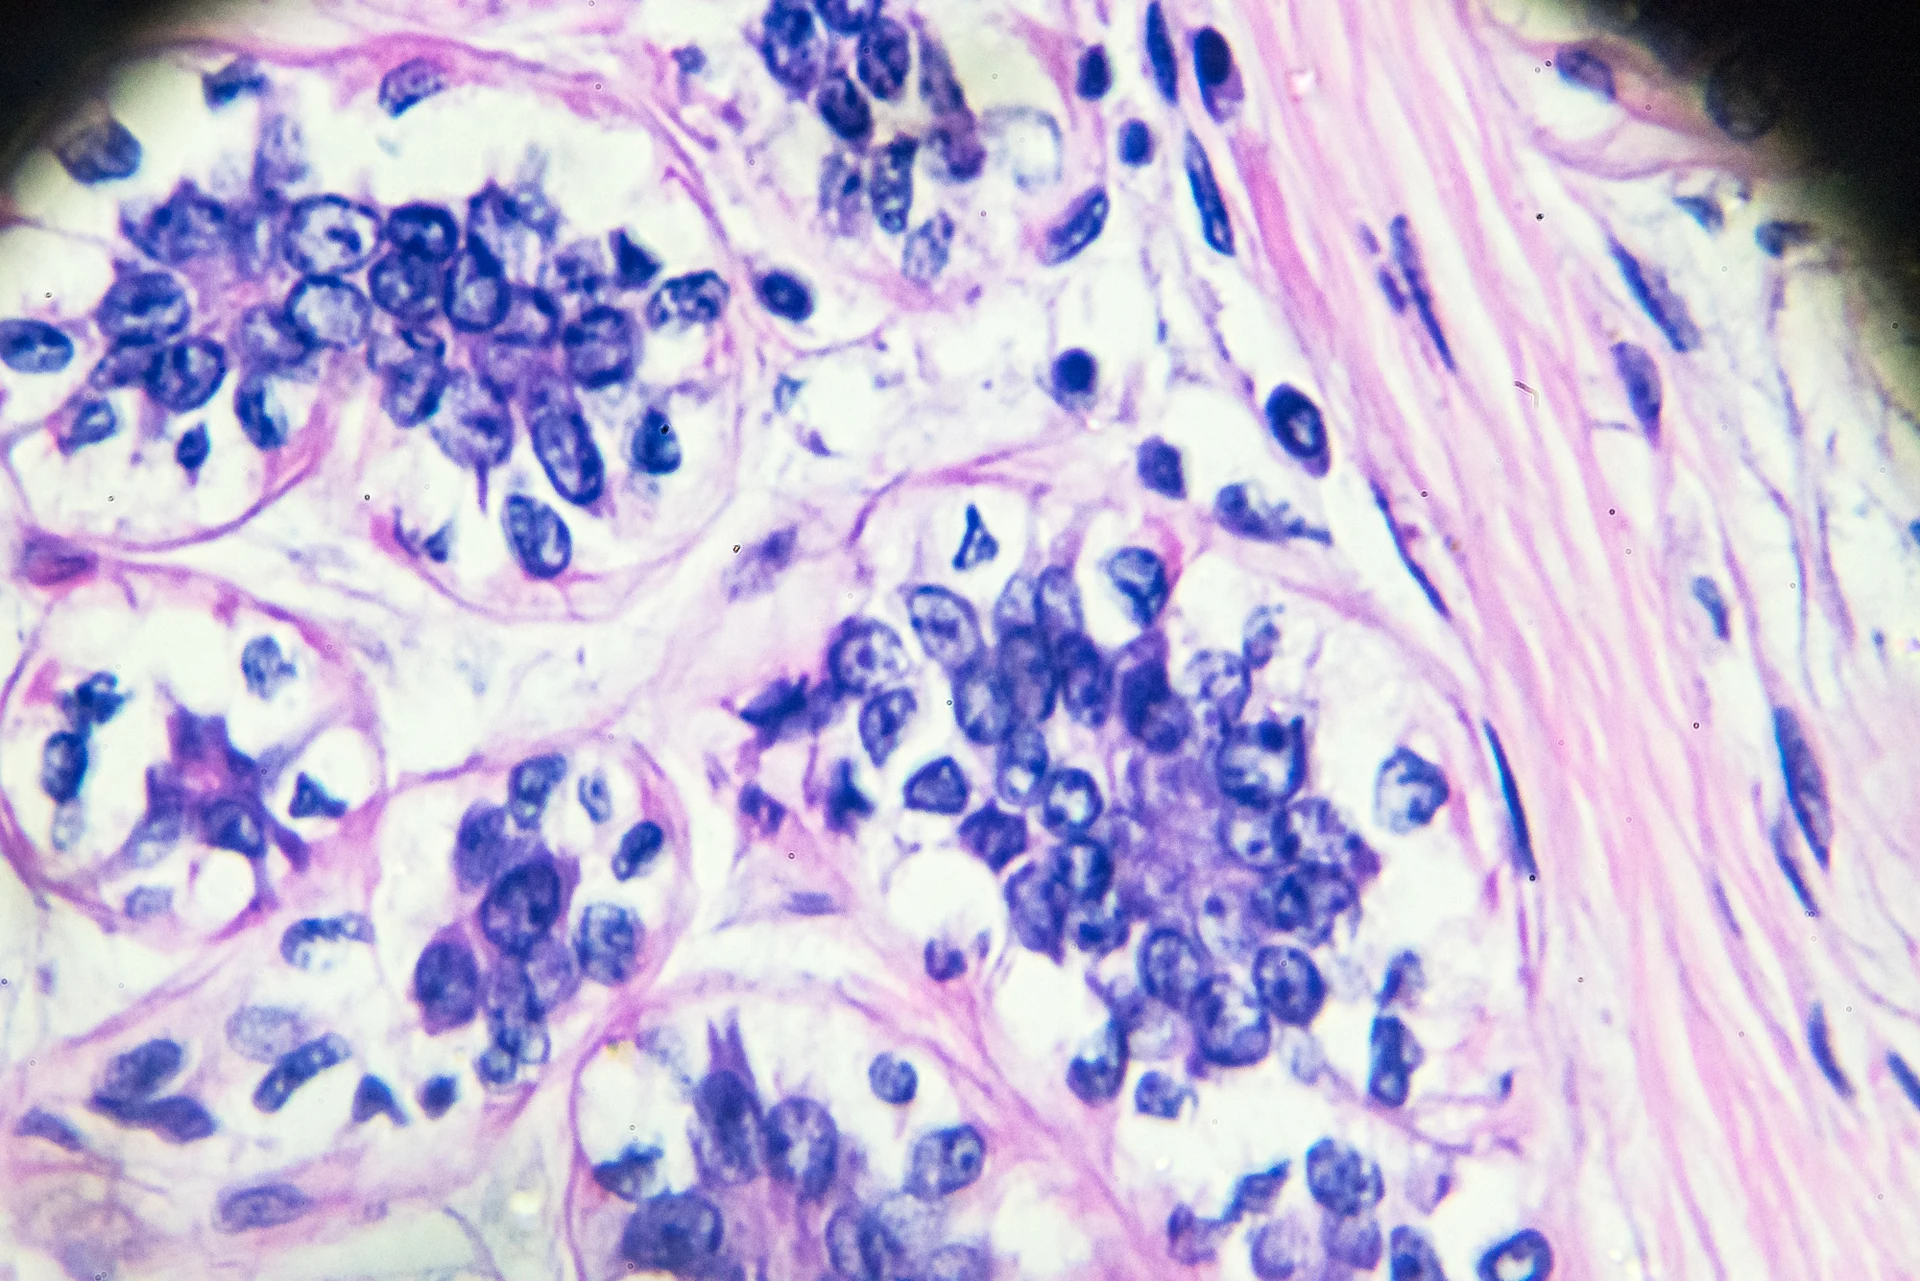

Cancer cell lines are cell lines that consist of “immortal” cancer cells that continually divide and grow over time under laboratory conditions. Human cancer cell lines are most commonly used to study cancer biology, identify new treatments and improve the efficacy of existing cancer treatments.